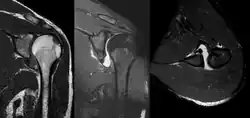

A diagnosis of shoulder dislocation is often suspected based on the person's history and physical examination. Radiographs are made to confirm the diagnosis. Most dislocations are apparent on radiographs showing incongruence of the glenohumeral joint. Posterior dislocations may be hard to detect on standard AP radiographs, but are more readily detected on other views. After reduction, radiographs are usually repeated to confirm successful reduction and to detect bone damage. After repeated shoulder dislocations, an MRI scan may be used to assess soft tissue damage. In regards to recurrent dislocations, the apprehension test (anterior instability) and sulcus sign (inferior instability) are useful methods for determining predisposition to future dislocation.

A Hill–Sachs lesion is an impaction of the head of the humerus left by the glenoid rim during dislocation.[6] Hill-Sachs deformities occur in 35–40% of anterior dislocations. They can be seen on a front-facing X-ray when the arm is in internal rotation.[11] Bankart lesions are disruptions of the glenoid labrum with or without an avulsion of bone fragment.[12]